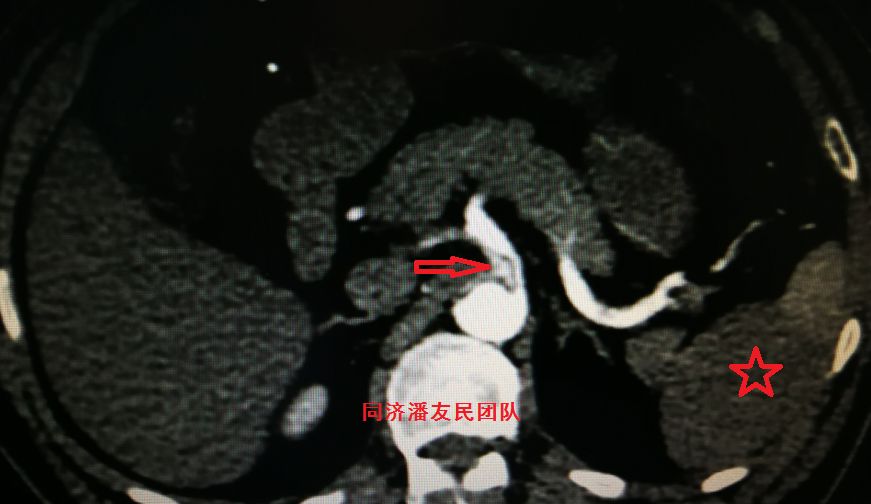

图9:CTA显示主动脉夹层累及腹腔干动脉,真腔狭窄(红箭头所示),同时显示脾脏部分梗死(红星形所示)

图10:CTA显示肠系膜上动脉由假腔供血(红箭头所示),真腔压闭,左肾及脾脏梗死(红星形所示)